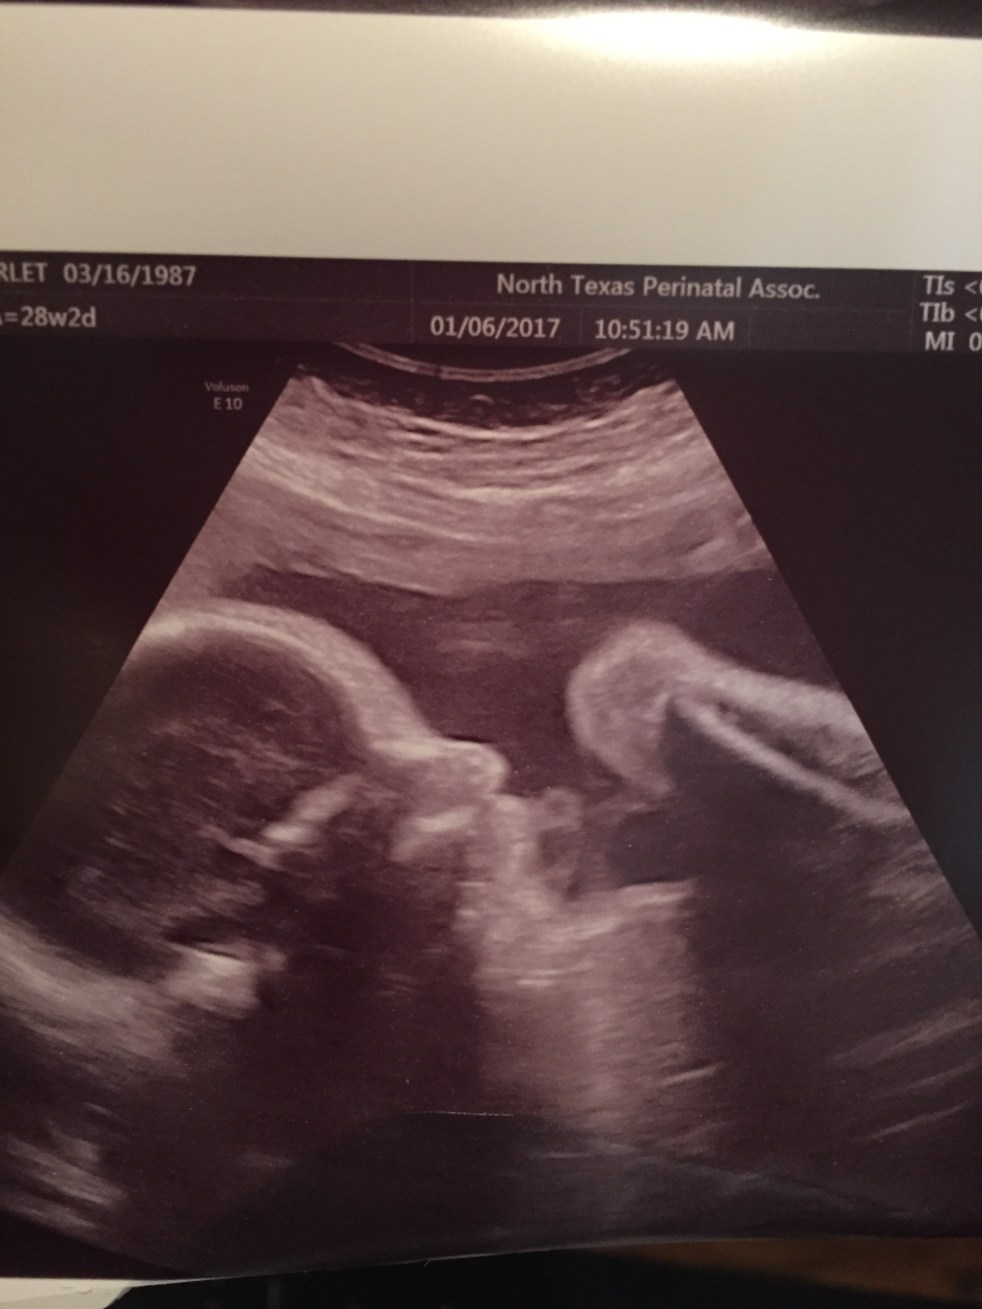

28 Week Bumpdate

January 7, 2017January 8, 2017 lifeonthebrightsidesite1 Comment

We have officially made it to the 3rd trimester! I am dancing while I type these words. I have not had a threat of pre-term labor but it still feels like an accomplishment to get to this point. We had two more appointments this week, one with our regular OB and another with the specialist.… Continue reading 28 Week Bumpdate